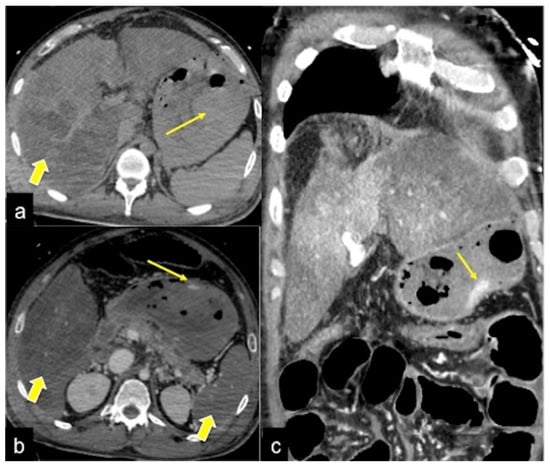

| Colorectal Cancer/Polyps (Figure 6, Figure 36, Figure 37 and Figure 38) | Bowel obstruction with or without bleeding. | Adenocarcinoma: irregular wall thickening with or without stenosis [25]; Polyps: mass-forming protrusions in the intestinal lumen with vascularised peduncle. |

| Inflammatory Bowel Disease (Figure 39 and Figure 40) | Haematochezia-rectorrhagia. | Acute: thickening of the walls, engorgement of the adjacent vasa recta, hyperaemia of the mucosa and infiltration of perirectal fat. Chronic: the colon and rectum are narrowed and shortened, without haustra, and with proliferation of the perirectal fat. |